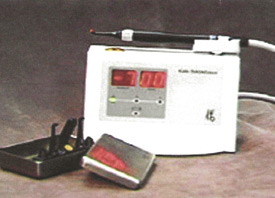

Cavities are difficult to diagnose Sometimes, it's difficult for us to diagnose cavities, especially in the pits and grooves on the biting surfaces of your back teeth. The traditional way to check for....